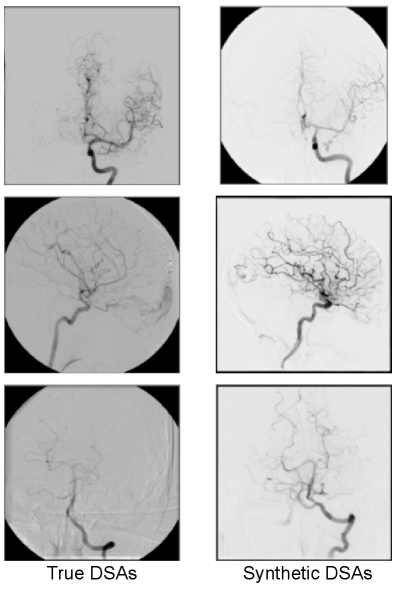

Refer to caption

Figure 2: Representative arterial-phase DSA frames from the clinical dataset (left column) and from the conditional diffusion model (right column)

These four conditions corresponded to the most frequently occurring anatomical-plane-angle combinations in our curated dataset, ensuring a representative basis for assessment. We generated 10 batches of 40 images sampled under the four conditions above in a stratified manner (10 images per condition per batch), for a total of 400 synthetic DSA frames. This design balances across condition frequencies observed in the real dataset, enabling per-condition analysis with matched sample sizes. Before conducting the reader study, we visually compared samples from the conditional diffusion model with real arterial-phase DSAs from the same anatomical territories. As illustrated in Fig. 2, the generated frames closely resemble clinical DSAs in terms of vessel topology and contrast dynamics, providing qualitative support that the model operates in a realistic image regime.